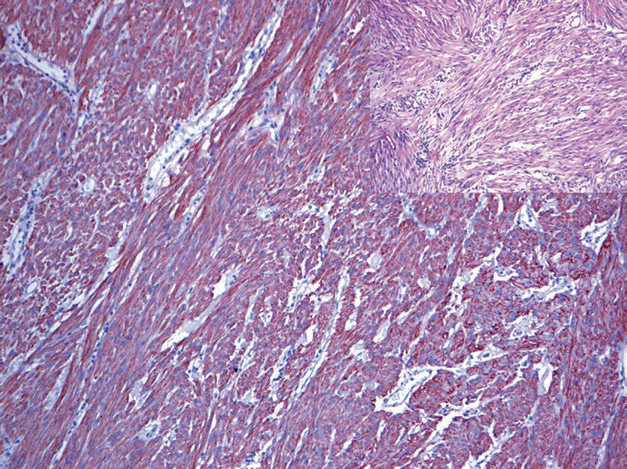

图1. 肠系膜纤维瘤病,β-catenin在细胞核强阳性表达。